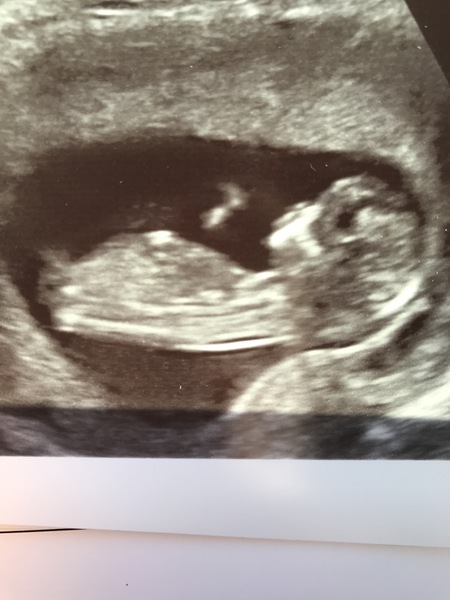

Any guesses

user1480264544 · 18/01/2017 13:22

Any guesses would be appreciated x

Boy I think